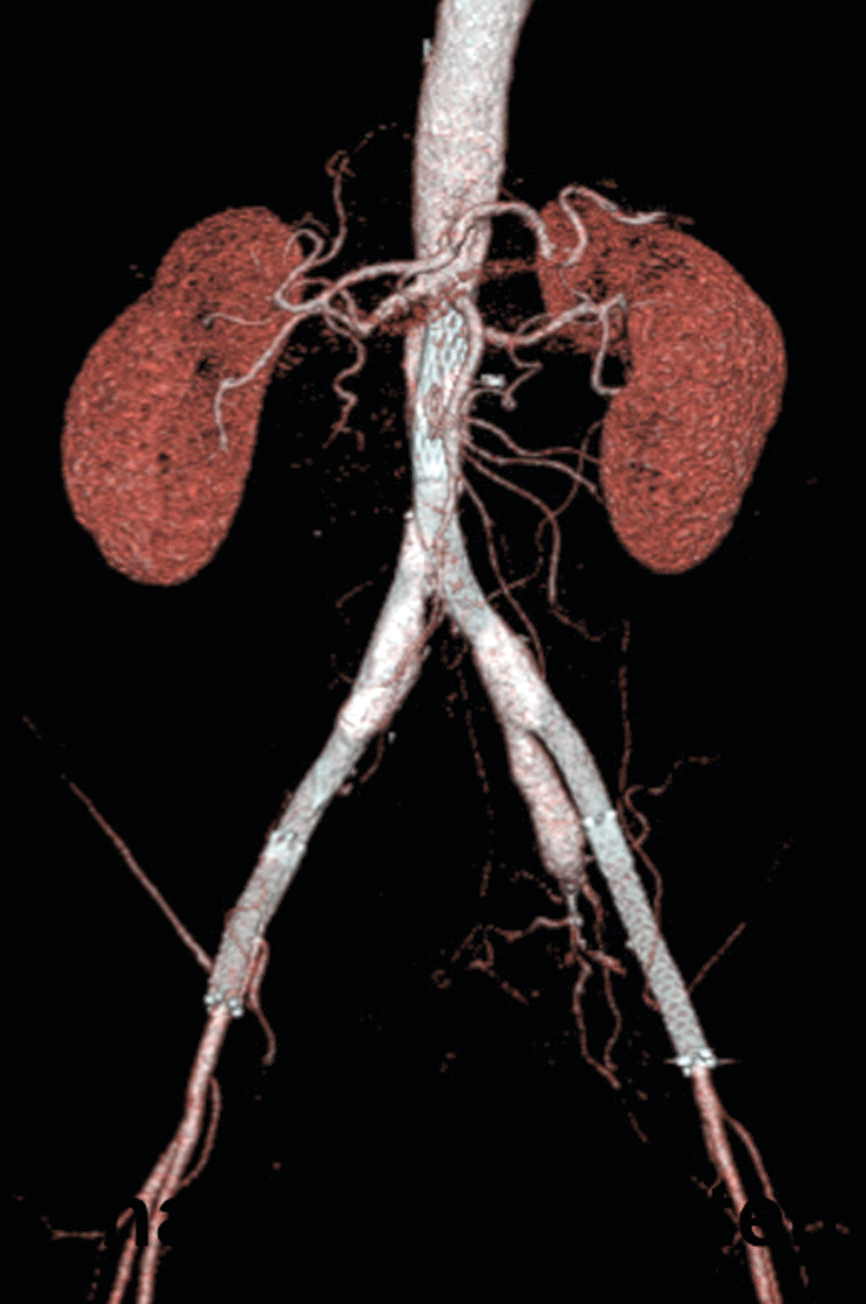

Abb. 2: Mit einem medikamentenbeschichteten Ballon ließ sich der langstreckige Verschluss der A. femoralis superficialis öffnen. Abb. 2: Mit einem medikamentenbeschichteten Ballon ließ sich der langstreckige Verschluss der A. femoralis superficialis öffnen. © Krankenberg H. Hamburger Ärzteblatt 2020; 74: 13-16 © Hamburger Ärzteverlag, Hamburg

Besonders häufig finden sich atherosklerotische Veränderungen in der A. femoralis superficialis, die ebenfalls einem erheblichen Bewegungsstress ausgesetzt ist. Läsionen in diesem Gefäß sollten bis zu einer Länge von 25 cm zunächst endovaskulär angegangen werden. Mit einer medikamentenbeschichteten Ballon-Angioplastie bleibt die Arterie länger offen als mit dem Standardballon (70 % vs. 45 %). Bei Residualstenosen oder fluss-limitierender Dissektion können zusätzliche Stents eingesetzt werden. Spot-Stenting kombiniert mit medikamentenbeschichteten Ballons hat sich bei längeren Läsionen bewährt. Patienten mit schwerer Kalzifikation profitieren von einer primären Stentimplantation. Direkte Vergleichsstudien Ballon vs. Stent fehlen allerdings bislang.